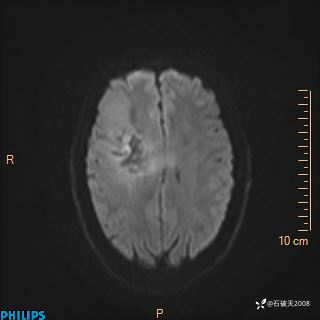

2024.2.21MR

ADC